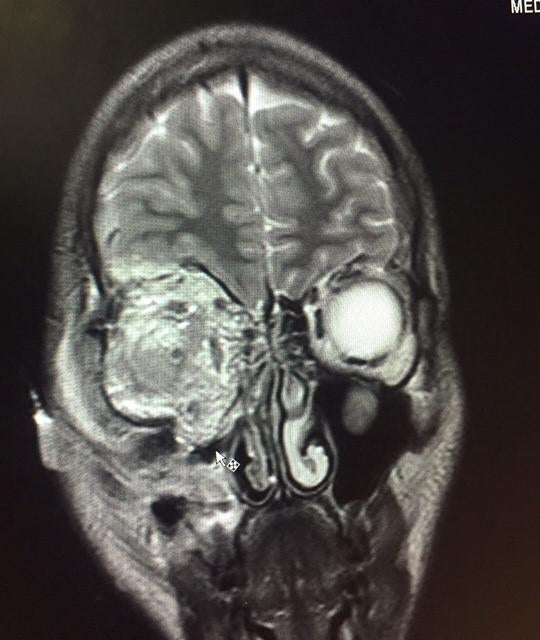

Security agents have also denied or failed to provide access to medical treatment to some detainees who had preexisting medical conditions or suffered serious injuries during their arrest and subsequent detention—including being shot with pellets at very close range.